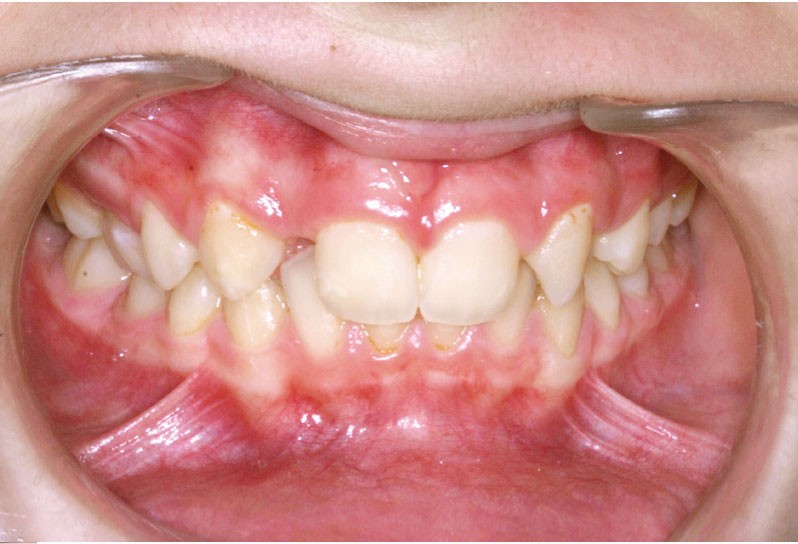

Ludivine T. âgée de 12 ans et demi présente une agénésie des deux incisives latérales maxillaires dans un contexte occlusal de classe II division 2 (fig. 1 à 3).

Les vues endo-buccales (fig. 2) montrent la classe II division 2 occlusale associée à une forte supraclusion incisive et l’évolution spontanée de 13 et 23 pratiquement en place de 12 et 22. Il persiste cependant un diastème disgracieux entre 13 et 11.